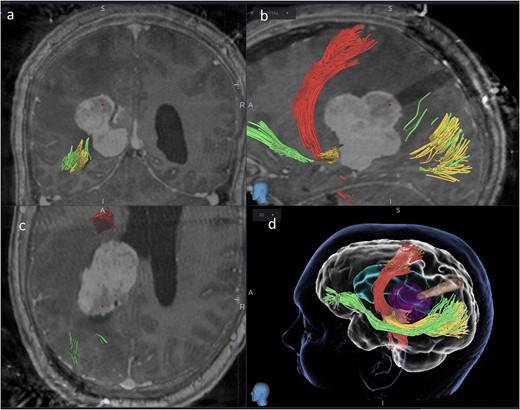

We hereby present the case of a 32-year-old gentleman referred to the neuro-oncology service with an 8-months history of left sided headaches, dizziness, and blurred vision. MRI head demonstrated a 50 × 52 × 51 mm lesion in the posterior horn of the left lateral ventricle, with extension into the periventricular white matter (Fig. 1). Following multi-disciplinary discussion, a plan was made for the patient to undergo a minimally invasive approach for resection of this lesion. Pre-operative cortical and subcortical mapping was performed with navigated transcranial magnetic stimulation (nTMS) and diffusion tensor imaging (DTI). The best trajectory was defined taking into consideration the localization of the cortico-spinal tract (CST, red), the inferior fronto-occipital fasciculus (IFOF, green) and the optic radiations (OR, yellow) (Fig. 2).

Coronal (a), sagittal (b) and axial (c) views of the merged images from intra-operative CT scans (O-Arm) with pre-operative MRI tractography. The tubular retractor is in situ. (d) Virtual 3D reconstruction of the tubular retractor (brown) in the merged images and its relationship with the tumour (purple), the CST (red), the IFOF (green), and the OR (yellow).